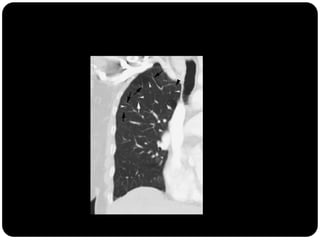

Alguns sinais e padrões

radiológicos de TÓRAX

Padrão de árvore em brotamento: Acúmulo de

secreções em pequenas vias aéreas ocorrendo

principalmente em infecções

Padrão de faveolamento